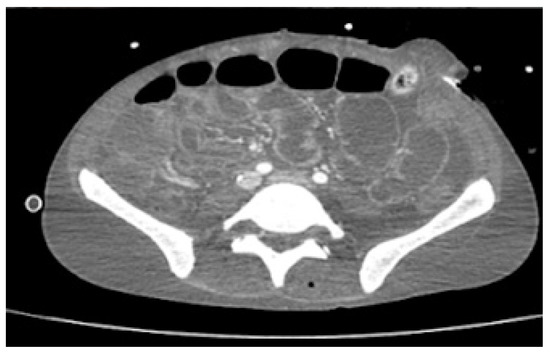

Despite being on ARV therapy since day +46 as previously mentioned, during an approximate three-week interval, HIV viral load increased from 36,904 (day +9) to 795,000 copies/mL (day +68). Additionally, on D6 of oral tecovirimat therapy, there was progression of skin ulcerations and extensive destruction of the perineum and gluteal region, with evidence of fistulization to rectum and prostate on abdominopelvic CT. For this reason, a protective colostomy was performed on day +73 to prevent contamination of the perineal lesions and allow for cicatrization to occur. In addition, CT scan showed jejunal and colic increased mucosal contrast uptake, suggesting enterocolitis (Figure 3). These facts raised concerns about probable insufficient enteric absorption of ART and tecovirimat considering the progressive gastric content stasis and enterocolitis documented on CT and therefore possible extension of inflammatory process to small bowel. This situation prompted the search of a parenteral option to both medications. On day +73 intravenous (IV), cidofovir (5 mg/kg once weekly for 2 weeks, then once every other week, following WHO interim guidance June 2022) was added to oral tecovirimat (which completed 21 days) as antiviral therapy for mpox. HIV viral load increased to 5,000,000 copies/mL, and TCD4+ dropped to 38/μL on day +75, and there was confirmation of no other mutation than M184V in contemporary resistance testing along with no mutations detected for the integrase gene. Together with viral enteropathy—the tissue had abundant inflammatory cell infiltrate and villous atrophy—reported in duodenal biopsy on day +86, which was also PCR-positive for mpox, confirmed the likely lack of absorption of oral BIC/TAF/FTC. A full parenteral regimen with intramuscular (IM) cabotegravir (CAB) and IM rilpivirine (RPV) was started on day +95, both to be administered monthly, with initial dosing of 600 mg of CAB and 900 mg of RPV together with IV zidovudine 50 mg every four hours. Six days after the initiation of the later regimen, there was already a decrease in HIV viral load from 5,000,000 to 9010 copies/mL (Table 1).

Figure 3. Abdominopelvic CT scan on day +73 with marked thickening of jejuno-ileum and colon mucosa, suggesting enterocolitis.